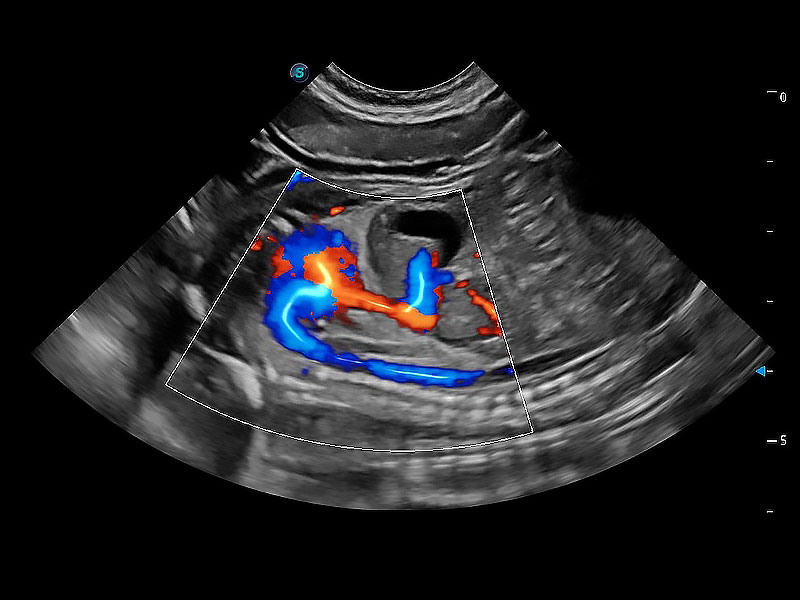

(犬)胎儿四腔心